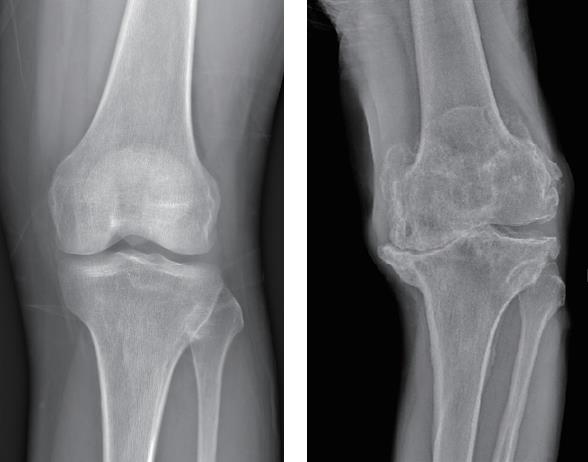

每个关节面都有软骨,它维持着关节活动的灵活和润滑,但关节软骨在损伤后修复能力有限。关节长期异常承重(如肥胖)、磨损(如长期不恰当的运动姿势)、外伤等,都会导致关节软骨变薄甚至消失。关节边缘的骨可能异常增生,破坏关节内的正常结构,从而出现疼痛、肿胀和关节活动受限。正常膝关节与慢性膝关节骨关节炎对比(X光片)如图1-6所示。

图1-6 正常膝关节与慢性膝关节骨关节炎对比(X光片)

注:左图是正常膝关节,右图是慢性骨关节炎患者的膝关节。可以看到,正常膝关节在X光片下显示均匀的关节间隙,这是由健康的关节软骨造成的。而慢性膝关节骨关节炎患者的膝关节间隙消失,关节周围骨赘形成,还出现了关节变形。